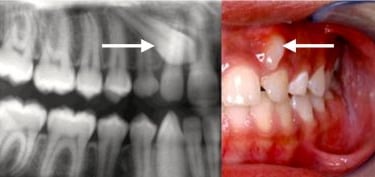

Dientes impactados

Los dientes impactados son dientes que no pueden erupcionar correctamente debido a la falta de espacio o a una obstrucción.

Los pacientes pueden notar que un diente no ha salido, aunque debería haberlo hecho. Esta condición es común con las muelas del juicio y los caninos superiores.

El tratamiento puede incluir la extracción del diente impactado o la creación de espacio para permitir su erupción.